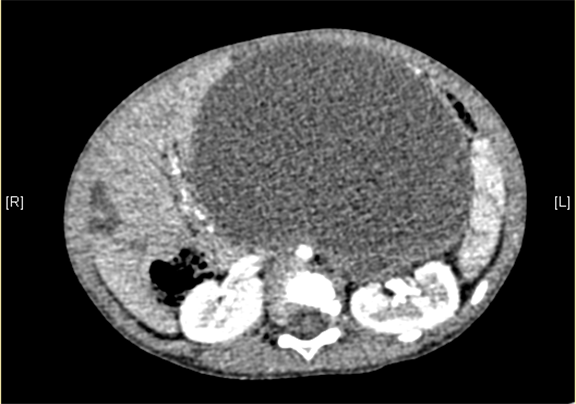

腹部三维动态CT:腹腔巨大囊性占位性病变,考虑肠系膜来源良性病变可能性大,腹腔肠系膜淋巴管瘤?

术前CT检查:

动脉期

静脉期

平衡期